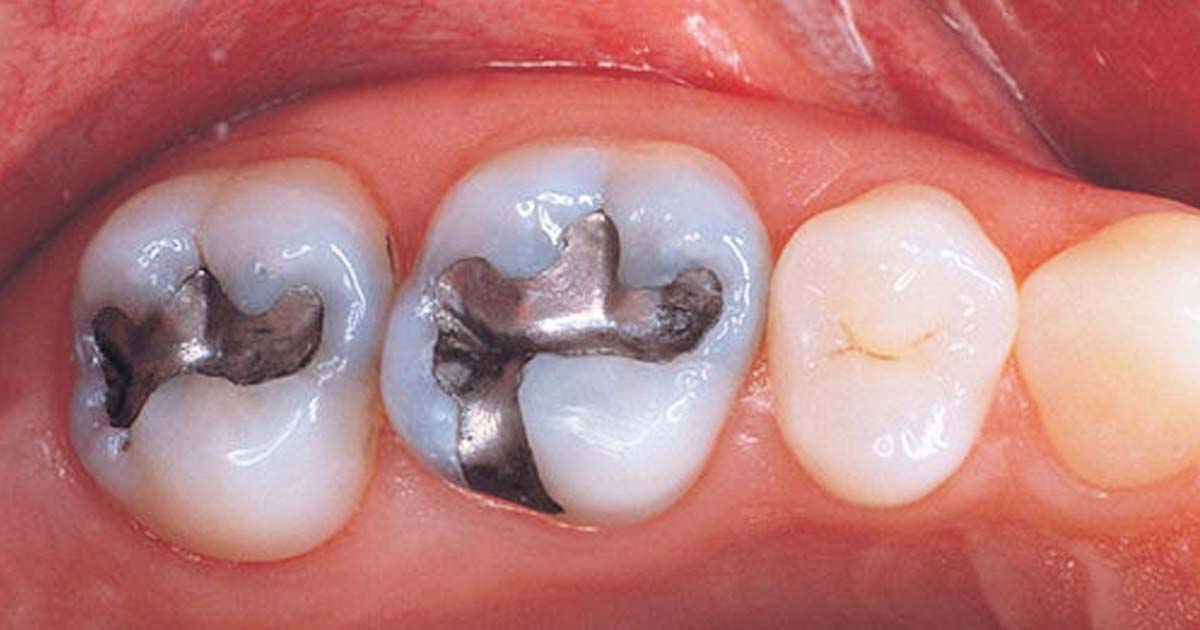

Amalgam restorations:

Amalgam restorations are taught in dental school right from the 2nd year of the dental course as pre-clinicals. From its manipulation to packing it in the cavity, everything is done by the students. This method is dangerous as the mercury present in the composition poses a threat not only to the student's health but also to the dental assistants and teachers present during college hours.

Other than the amalgam usage during pre-clinicals, amalgam restorations are also performed during clinicals by these students when they are promoted to the final year. This increases the exposure to patients who will have mercury content in their oral cavity for years after the procedure is done in a dental college. Amalgam fillings not only weaken the tooth but are also capable of causing neurological impairment or kidney dysfunction.

With new materials being introduced frequently, it is easier for dentists to explore and learn new techniques. These materials are more biocompatible, safe, cost-effective, and easier to use than traditional restorative materials like amalgam. Restorative materials like Glass Ionomer Cement and resin-based composites, etc. can be used to restore dental cavities. These do not pose health hazards, as seen in the case of amalgam.